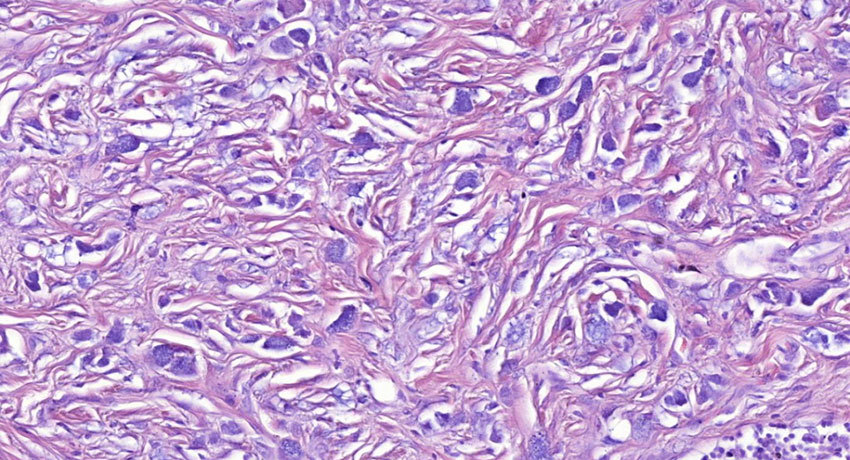

Перстневидноклеточный рак — гистологический тип злокачественных опухолей. Он получил свое название из-за характерного внешнего вида раковых клеток под микроскопом: большую часть клетки занимают вакуоли (пузырьки), заполненные муцином (слизью). При этом клеточное ядро оттеснено к периферии.

Перстневидно-клеточные карциномы — разновидность аденокарцином, злокачественных опухолей из железистых клеток. Они являются низкодифференцированными, то есть опухолевые клетки утрачивают черты нормальных, между ними исчезают плотные контакты, утрачиваются межклеточные взаимодействия. Такие злокачественные опухоли быстро прогрессируют, рано метастазируют, отличаются менее благоприятным прогнозом по сравнению с другими видами рака.

В результате активации PI3K усиливается выработка муцинов — основного компонента секрета слизистых желез. Один из них, Muc4, активирует ErbB2. В норме эти два вещества разделены, но при перстневидноклеточном раке они взаимодействуют, замыкается порочный круг. Между клетками утрачиваются контакты, они быстро, бесконтрольно размножаются и производят много слизи.